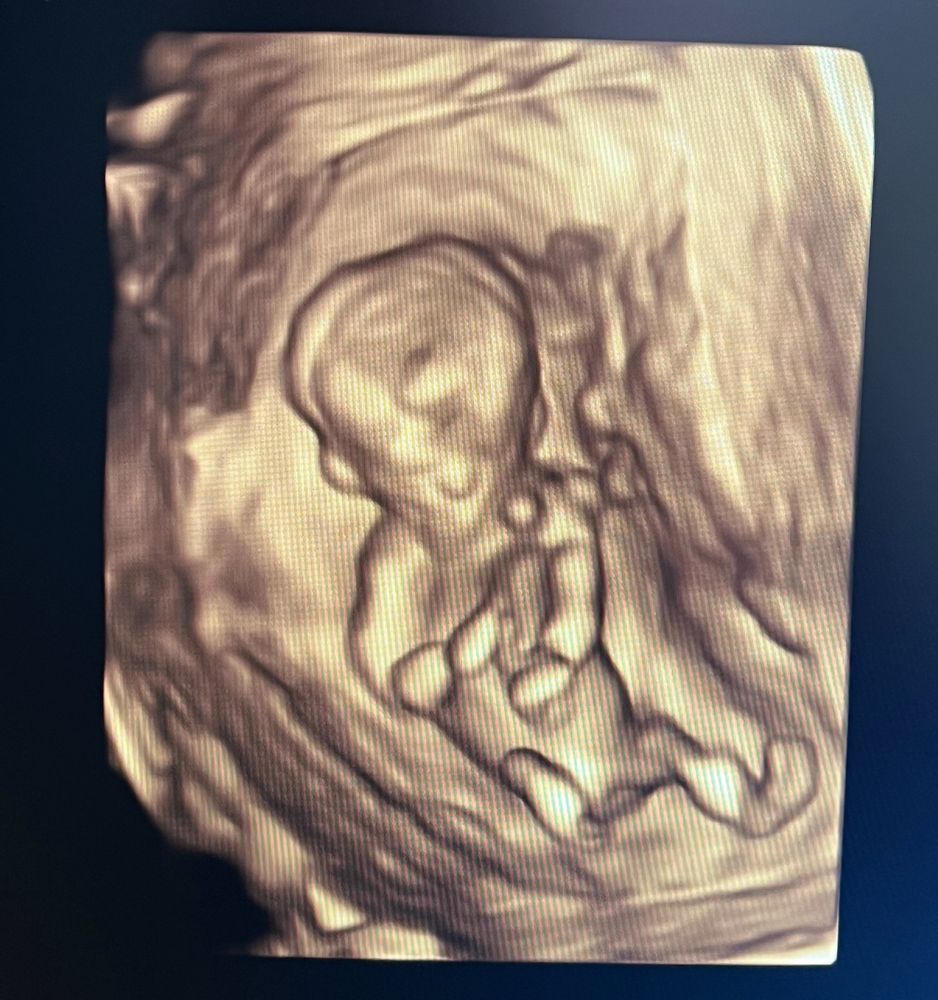

Скрининг 1 , определим пол?

Врач сказала, что может предположить пол, но говорить не будет, это ее принцип. А мне конечно интересно) кто разбирается, видно мальчик или девочка?

12 недель 5 дней

Буду мамой дочки

Я за девочку 🐣